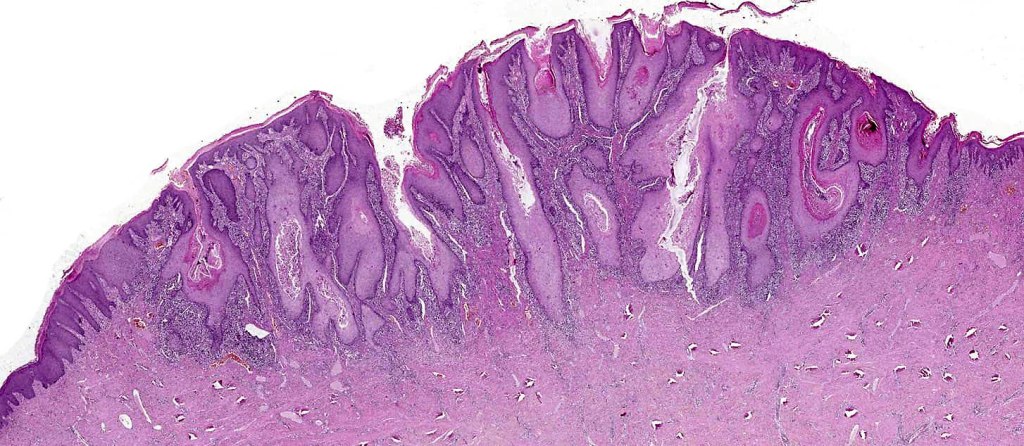

•Often massive hyperkeratosis

•Epidermal verrucous hyperplasia

•Deeply penetrating bulbous processes with a pushing rather than infiltrating lower border